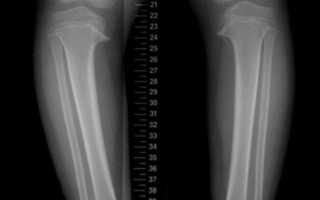

Рентгенограмма при болезни Блаунта

Последние две процедуры являются вспомогательными, а основу диагностики составляет рентгенография, поскольку рентгеновский снимок укажет на:

- искривление большой берцовой кости — деформация будет иметь вид клюва;

- равномерную вогнутую форму суставной поверхности этой кости, которая также будет скошена под углом. Нередко обнаруживается высокая минерализация;

- расширенную область роста внутренней части поражённой кости;

- нечёткие контуры костно-замыкательной пластинки;

- утолщение кортикального слоя;

- наслаивание теней малой и большой берцовой кости.